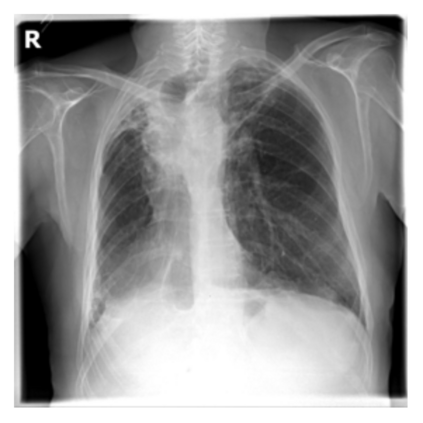

The evaluation of infectious disease processes on radiologic images is an important and challenging task in medical image analysis. Pulmonary infections can often be best imaged and evaluated through computed tomography (CT) scans, which are often not available in low-resource environments and difficult to obtain for critically ill patients. On the other hand, X-ray, a different type of imaging procedure, is inexpensive, often available at the bedside and more widely available, but offers a simpler, two dimensional image. We show that by relying on a model that learns to generate CT images from X-rays synthetically, we can improve the automatic disease classification accuracy and provide clinicians with a different look at the pulmonary disease process. Specifically, we investigate Tuberculosis (TB), a deadly bacterial infectious disease that predominantly affects the lungs, but also other organ systems. We show that relying on synthetically generated CT improves TB identification by 7.50% and distinguishes TB properties up to 12.16% better than the X-ray baseline.